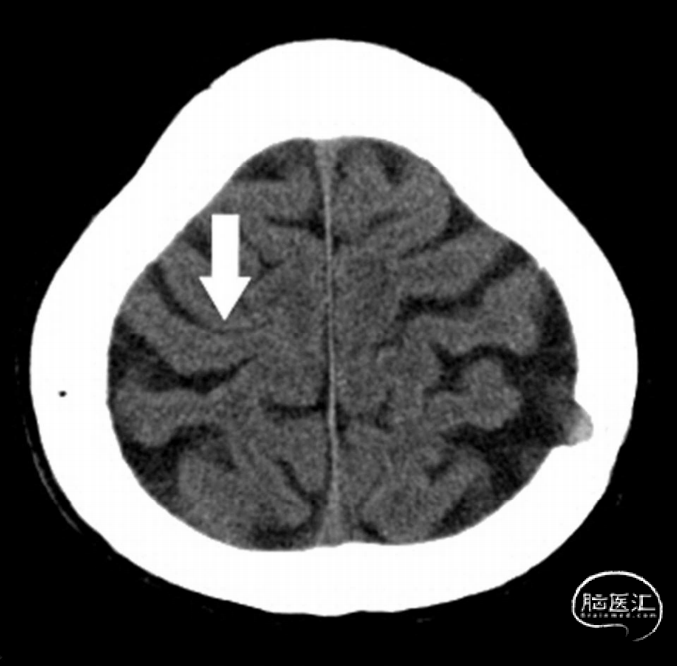

case2

间断头疼入院,脑CT为高信号

上面的病例,是韩国学者发表的文献,也是这样一个表现,不知道大家能把他是否能一眼就看出它是蛛网膜下腔出血?还是皮层静脉血栓?

研究者在进行了CTA检查没有特殊发现,然后进行了一系列的磁共振:FLAIR、梯度回波、SWI以及ADC影像,最后是通过造影检查确诊。

研究者反复地去比对高信号的区域以及DSA上所显示的充盈缺损的区域,最终判断出这是一个皮层静脉血栓,而不是其他的疾病。通过上面的两个例子,我们得出皮层静脉血栓的鉴别的方法: